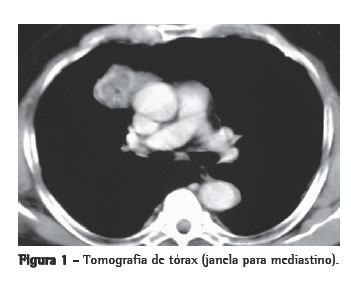

Paciente de 66 anos, do sexo masculino, natural de São Luiz (MA) e procedente de São Paulo, sem antecedentes mórbidos e sem história de tabagismo, foi admitido no ambulatório sem queixas e em bom estado geral. Trazia exame radiológico, realizado em outro serviço há dez anos, revelando a presença de tumor de mediastino anterior, com cerca de 4 cm de diâmetro. A investigação prosseguiu com a realização de uma nova radiografia e uma nova tomografia computadorizada de tórax, as quais revelaram um tumor de contornos espiculados, medindo 3,0 × 4,0 cm, localizado no mediastino anterior à direita e com as mesmas características encontradas nos exames realizados anteriormente (Figura 1). Apresentava exames laboratoriais e prova de função pulmonar normais. Os marcadores tumorais estavam normais. Foi confirmado o diagnóstico sindrômico de tumor de mediastino anterior, e indicado tratamento operatório.